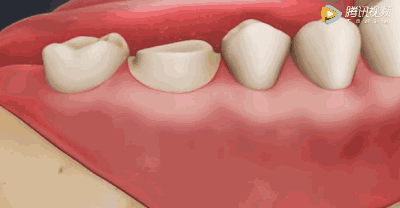

一般来说,当牙髓发生炎症,就会引起一定程度的疼痛,医学上称为“牙髓炎”。日常的吃药打针,只能暂时地缓解疼痛,治标不治本。

而且,如果炎症不能得到很好的控制,炎症物质和病菌就会蔓延到牙根周围,破坏范围更大,这会给患者带来更大的痛苦。

牙髓炎症的发展